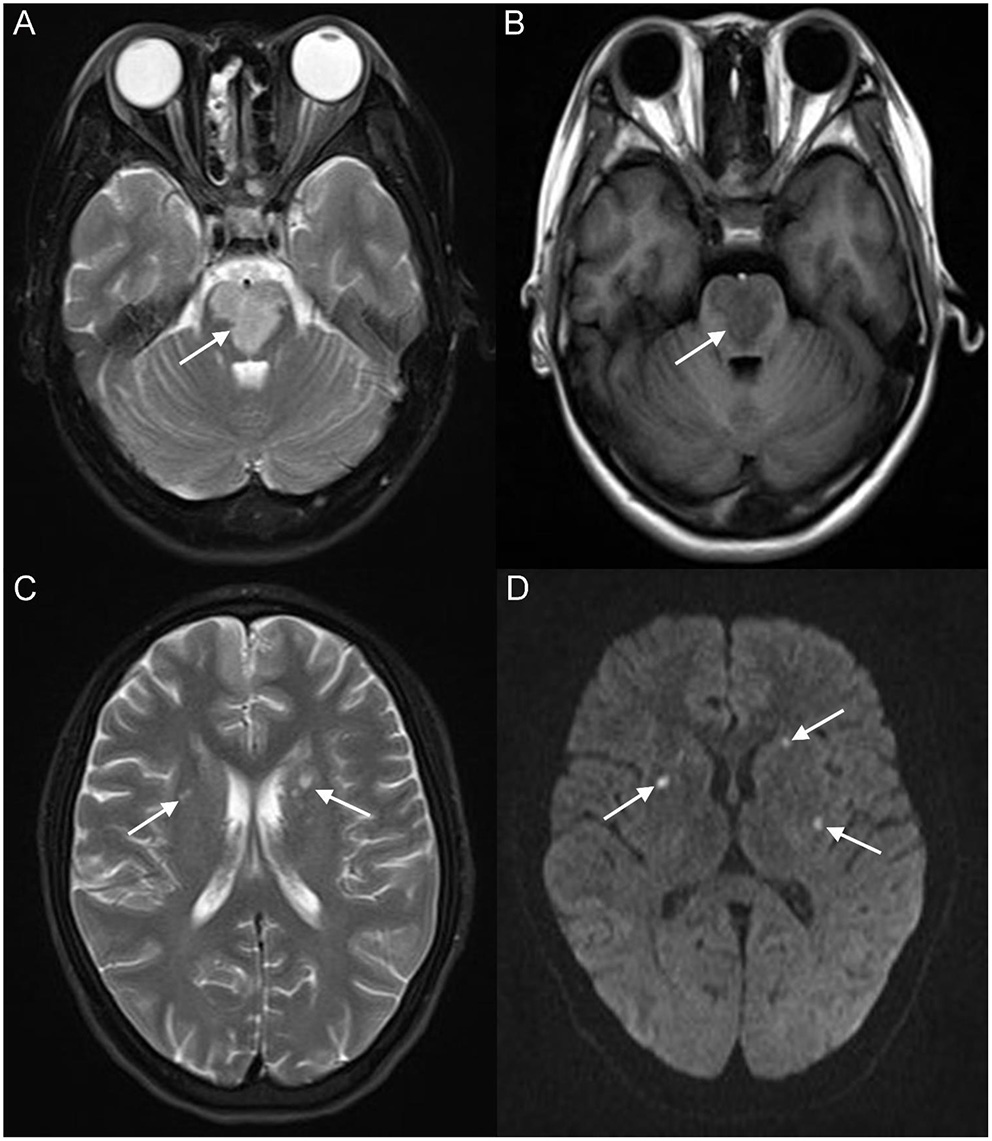

Figure 3

Brain magnetic resonance imaging (MRI) revealed extensive hyperintensity on T2-weighted imaging and hypointensity on T1-weighted imaging of the bilateral parts of the pons (white arrow) (A,B); a patchy hyperintensity on T2-weighted imaging of the bilateral basal ganglia, bilateral centrum semiovale (white arrow) (C), and right frontoparietal lobe, which presented a high signal on diffusion-weighted imaging (DWI) (white arrow) (D).

A 17-year-old girl presented to our hospital on August 22, 2021 with clouding of consciousness for more than 3 days. At 3+days prior, the patient was unable to speak the patient was unable to speak when called softly and unable to open the right eye, combined with involuntary movements of the limbs and incontinence. The patient visited the local hospital immediately, where relevant tests were performed, suggesting intracranial lesions. Since the specific treatment measures were unavailable at the previous hospital, she was transferred to our hospital for further treatment. There was no history of trauma or familial genetic diseases, such as high blood pressure and diabetes. Physical examination revealed a body temperature of 37.0°C, heart rate of 110 bpm, regular heart rhythm, blood pressure of 113/77 mmHg, and no pathological murmurs in the valve region; pulmonary auscultation revealed coarse rales in the entire lung. The pupils were equal, round, and pupillary light reflexes were delayed. Both lower limbs exhibited hypertonia and hyperreflexia of the knee and tendon reflexes. Laboratory examinations revealed the following levels (normal range): coagulation function test showed D-dimer was 0.57 mg/L (< 0.5 mg/L) and fibrinogen was 5.82 g/L (2.00–4.00 g/L). Routine blood tests showed that the absolute value of neutrophils was 7.38 × 109/L (1.8 × 109/L−6.3 × 109/L). Infection-related markers showed that the hypersensitive C-reactive protein level was 111.563 mg/L (0.068–8.200 mg/L). Creatine kinase, α-hydroxybutyrate dehydrogenase, and lactate dehydrogenase levels were 148 U/L (26–140 U/L), 218 U/L (90–180 U/L), and 295 U/L (140–271 U/L), respectively. Computed tomography pulmonary angiography (CTPA) detected filling defects in the right atrium, left atrium, and left lower pulmonary basilar artery (Figure 1), and a diagnosis of Pulmonary embolism was made. Transthoracic echocardiography (TTE) revealed irregular iso-echoic masses in the bilateral atrium that were likely myxomas, given their location and appearance in a young patient; the myxoma in the left atrium measured approximately 38 × 21 mm, and it was attached to the junction of the lower part of the interatrial septum (IAS) and the root of the anterior mitral leaflet; in the right atrium it measured approximately 51 × 27 mm, and it was attached to the lower part of the IAS (Figure 2A). These masses resulted in the acceleration of the tricuspid valve antegrade flow (Figure 2B). Craniocerebral computed tomography (CT) showed extensive hypodensity in the bilateral parts of the pons and patchy hypodensity in the left corona radiata area and bilateral basal ganglia areas. Magnetic resonance imaging (MRI) also revealed extensive hypointensity on T1-weighted imaging and hyperintensity on T2-weighted imaging in the bilateral parts of the pons, and a patchy hyperintensity on T2-weighted imaging in the bilateral basal ganglia areas; bilateral centrum semiovale; and right frontoparietal lobe, which presented as high signal on diffusion-weighted imaging (DWI) (Figure 3). This confirmed the diagnosis of brain ischemia. To prevent thrombosis, low molecular weight heparin calcium (subcutaneous injection, 0.4 ml/12 h) was commenced on the second day of admission and continued until discharge. The patient underwent successful removal surgery for a biatrial myxoma. The masses were sent for histological examination, which confirmed the presence of a myxomatous matrix containing myxoma cells (Figure 4). The patient recovered uneventfully and was discharged 9 days after the procedure. The patient has been followed-up postoperatively for over 2.5 months, and limb motor function of the patient has recovered to some degree, but there is intellectual and cognitive decline.

Cardiac myxoma may cause embolic events during tumor tissue shedding, and cases of obstruction are relatively common in cardiac myxomas, and the morbidity rate of embolism is approximately 30–40% (14). Neurologic events are the most common embolic events followed by systemic embolic events, typically occurring at a rate of 42 and 29%, respectively. However, pulmonary embolic events are rare (15). Pulmonary embolism and cerebral stroke are uncommon but extremely significant complications of cardiac myxoma, with the risk of embolic events in cases of cardiac myxoma associated with the mass's appearance; typically, villous myxomas are more likely to cause embolism (16). Acute embolic stroke occurs when shedding tumor tissue reaches the cerebrovascular system, and it is often associated with high rates of mortality and disability, which poses a great risk to the life of the patients. Atrial myxomas have become a potential source of emboli; therefore, the primary presentation of many patients with a clinical history of myxomas is stroke (17, 18). In our case, the primary reason for the patient to go to the hospital for treatment was unconsciousness. Brain MRI revealed territorial cerebral infarction in the bilateral parts of the pons and small area cerebral infarction in the bilateral basal ganglia areas, bilateral centrum semiovale, and right frontoparietal lobe.